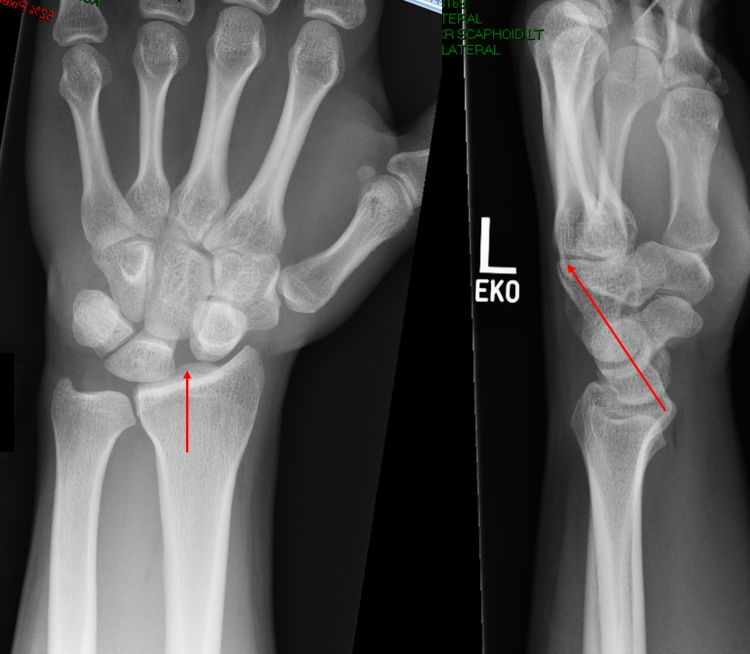

The diagnosis is usually made on an X-ray of the wrist. You can see on the X-ray below that the gap between the scaphoid and the lunate on the left is much bigger now than it was in the normal X-ray above, and the bones are no longer lined up the way they were.

On the side view, the lunate bone has sprung back to point slightly backwards compared to the normal xray. Often, the diagnosis will be confirmed on an MRI scan of the wrist.